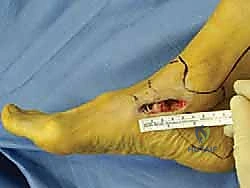

الخطوة الثالثة: الشق الجراحي والوصول الآمن

يتم عمل شق جراحي دقيق ومدروس على الجانب الداخلي للكاحل، خلف وتحت الكعب الإنسي. يستخدم الدكتور هطيف تقنيات تشريحية دقيقة لحماية الهياكل الحيوية المحيطة، وخاصة العصب الصافن (Saphenous Nerve) والوريد المرافق له، لتجنب أي تنميل أو ألم عصبي مزمن بعد الجراحة.